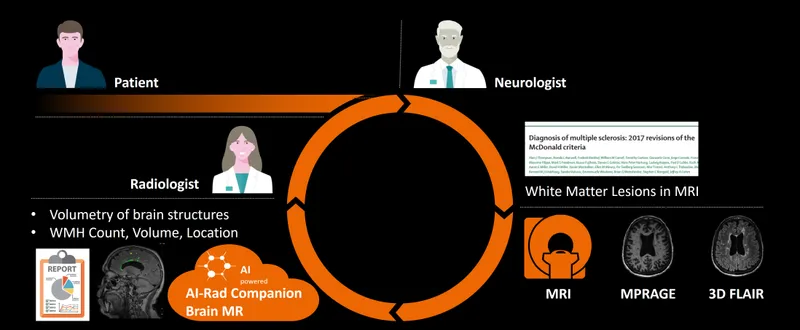

本ソフトウェアはクラウド(またはオンプレミス)環境で頭部MR画像から脳の各部位を自動的にセグメンテーションし、部位ごとの体積を自動計測します。 また白質の高信号領域の自動検出機能も備わっています。

想定効果

本ソフトウェアはアルツハイマー型認知症やパーキンソン病、多発性硬化症等のリスク評価に活用していただくことを想定しています。

サービスの特長

AI-Rad Companion Brain MRは後処理用の画像解析ソフトウェアで、臨床医による脳MR画像の表示、解析および評価を支援します。 以下の各種機能が備わっています。 ・各脳構造の自動セグメンテーションと定量解析 ・各脳構造の健常者集団から得た基準データとの定量比較 ・白質の高信号領域の自動検出機能 ・レポート作成のための結果表示(数値及び視覚化情報をすべて含む)

MPRAGE画像シリーズでの使用になります。またシリーズが非造影で撮像されている必要があります。 推奨スキャンパラメータに関してはお問い合わせください。 本ソフトウェアは医師の読影を補助する医療機器プログラムであり、診断を行う医療機器プログラムではありません。そのため、診断は医師の責任において行ってください。